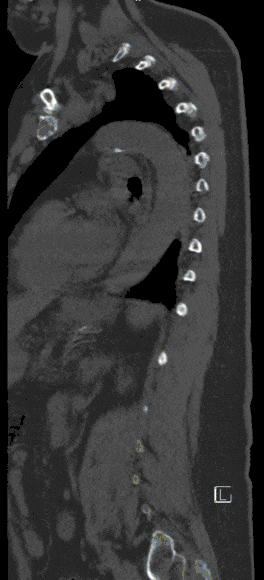

Vertebral Fractures

Vertebral body fractures are treated in-house in close interdisciplinary cooperation with the University Department of Trauma Surgery.

Injuries to the spine can lead to damage to the spinal cord and nerves, ranging from mild neurological disorders to paraplegic syndromes.

A treatment plan is created for each patient based on their injury pattern. Depending on the severity of the injury, subsequent care in a rehabilitation clinic may also be necessary.